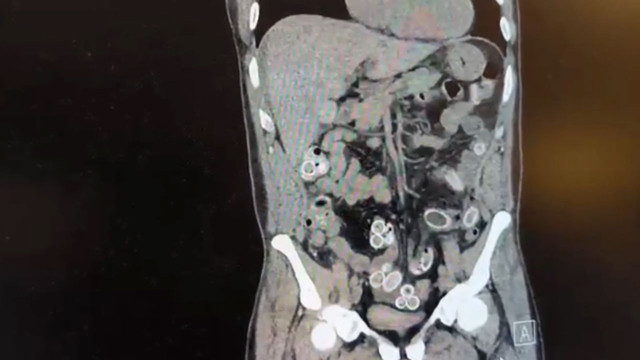

Yapılan muayenenin ardından çekilen tomografide Cüneyt Ç.’nin mide ve bağırsaklarında yabancı maddeler tespit edildi. Bunun üzerine hastane durumu polis ekiplerine bildirdi. İhbar sonrası Beşiktaş Asayiş Büro Amirliği ekipleri konuyla ilgili çalışma başlattı.

Doktorların değerlendirmesi sonrası ameliyata alınan Cüneyt Ç.’nin mide ve bağırsaklarından kapsül halinde toplam 49 adet esrar macunu çıkarıldı. Kapsüllerin toplam ağırlığının 259,7 gram olduğu öğrenildi. Şüpheliye ait bir cep telefonu da inceleme yapılmak üzere polis ekiplerine teslim edildi.